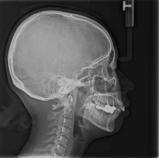

头侧片示:上颌前突、下颌后缩、高角、上前牙轴正常、下前牙唇倾。正畸诊断:凸面型,骨性Ⅱ类高角,安氏Ⅱ1s类。